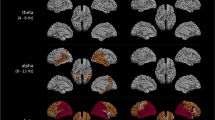

The whole-group LMM analysis revealed significant regional and global oscillatory slowing over time in our Aβ + AD cohort (N = 148), with strongest effects for regional measures. We found a significant increase in parieto-occipital, temporal, and global relative theta power, as well as a significant decrease in parieto-occipital, temporal and global relative beta power (Fig. 2A-C) and parieto-occipital peak frequency (Fig. 2D) over time. Although we report no significant longitudinal changes in functional connectivity strength and signal variability on whole-group level, estimates of regression coefficient β indicate a downward trend in parieto-occipital, temporal, and global AEC-c alpha and beta and JPEinv theta connectivity, as well as PE theta. PLI theta and wSMI theta connectivity exhibit a consistent positive trend across all regions. Regression coefficients and 95% confidence intervals are reported in Table 4. Regression coefficient β reflects the change in outcome measure per month. For visualization purposes, only significant estimates are plotted in Fig. 2.

Electrophysiological deterioration was most prominent in MCI subjects, reflected by significant development of 6 EEG measures over time (Fig. 3A-F). Similar to the whole-group analysis, strongest effects were reported for regional measures (Tables 5 and 6). We found a significant increase in parieto-occipital, temporal, and global relative theta power (Fig. 3A-C), while a significant decrease was demonstrated for parieto-occipital, temporal, and global relative beta power (Fig. 3D-F). The AD dementia group showed a significant decrease of the parieto-occipital peak frequency and temporal PE theta over time. The direction of reported effects for the remaining measures was largely similar across groups (Tables 5, 6 and 7). We report a downward trend (although not significant) in parieto-occipital, temporal, and global AEC-c beta, relative alpha2 power and PE theta, as well as a positive trend in PLI theta connectivity. Global and temporal alpha1 power and JPEinv connectivity decreased in both groups, whereas wSMI theta connectivity increased over time.

A-F Estimated trajectories and 95% confidence intervals for EEG measures in Aβ + MCI or AD dementia patients. Significant group-wise estimates are visualized (p < .05). A-C Parieto-occipital, temporal, and global relative theta power, MCI (yellow). D-F Parieto-occipital, temporal, and global relative relative beta power, MCI. G Parieto-occipital peak frequency (in Hz), AD dementia (blue). H Temporal permutation entropy (PE) theta, AD dementia